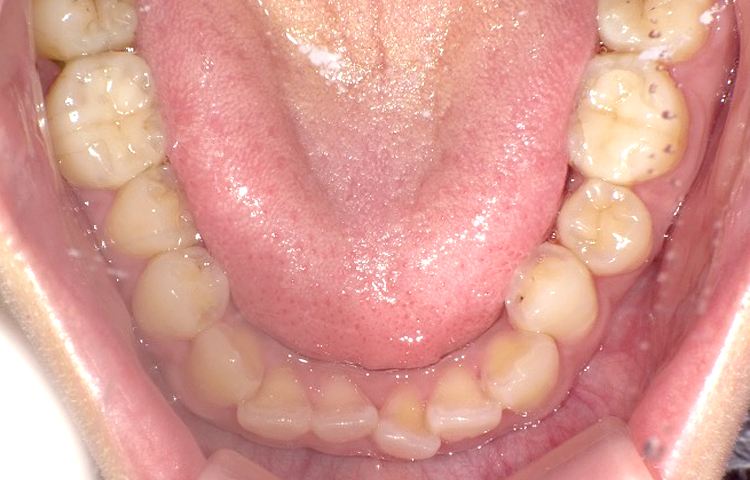

症例3

治療前

治療後

| 主訴 | 上下前歯全体の歯並びが気になる |

|---|---|

| 治療 期間 |

約6ヶ月 |

| 治療費 | 330,000円(税込)/調整費用別途 |

| 治療 内容 |

上下の前歯部にワイヤーを着けて進めていく、プチ矯正で施術。 |

| 治療の リスク |

固定の装置をつけないと後戻りしてしまう。 |